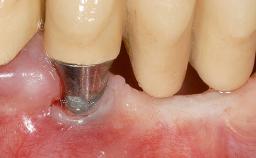

Early Implant Placement, Contour Augmentation, and Autologous Connective-Tissue Graft Using a Tunneling Technique to Replace an Upper Incisor with Generalized Gingival Recession

| # of Implants | 1 |

| Type of Implants | Reduced-Diameter|Two-Piece |

| Attachment | Reduced-Diameter|Two-Piece |